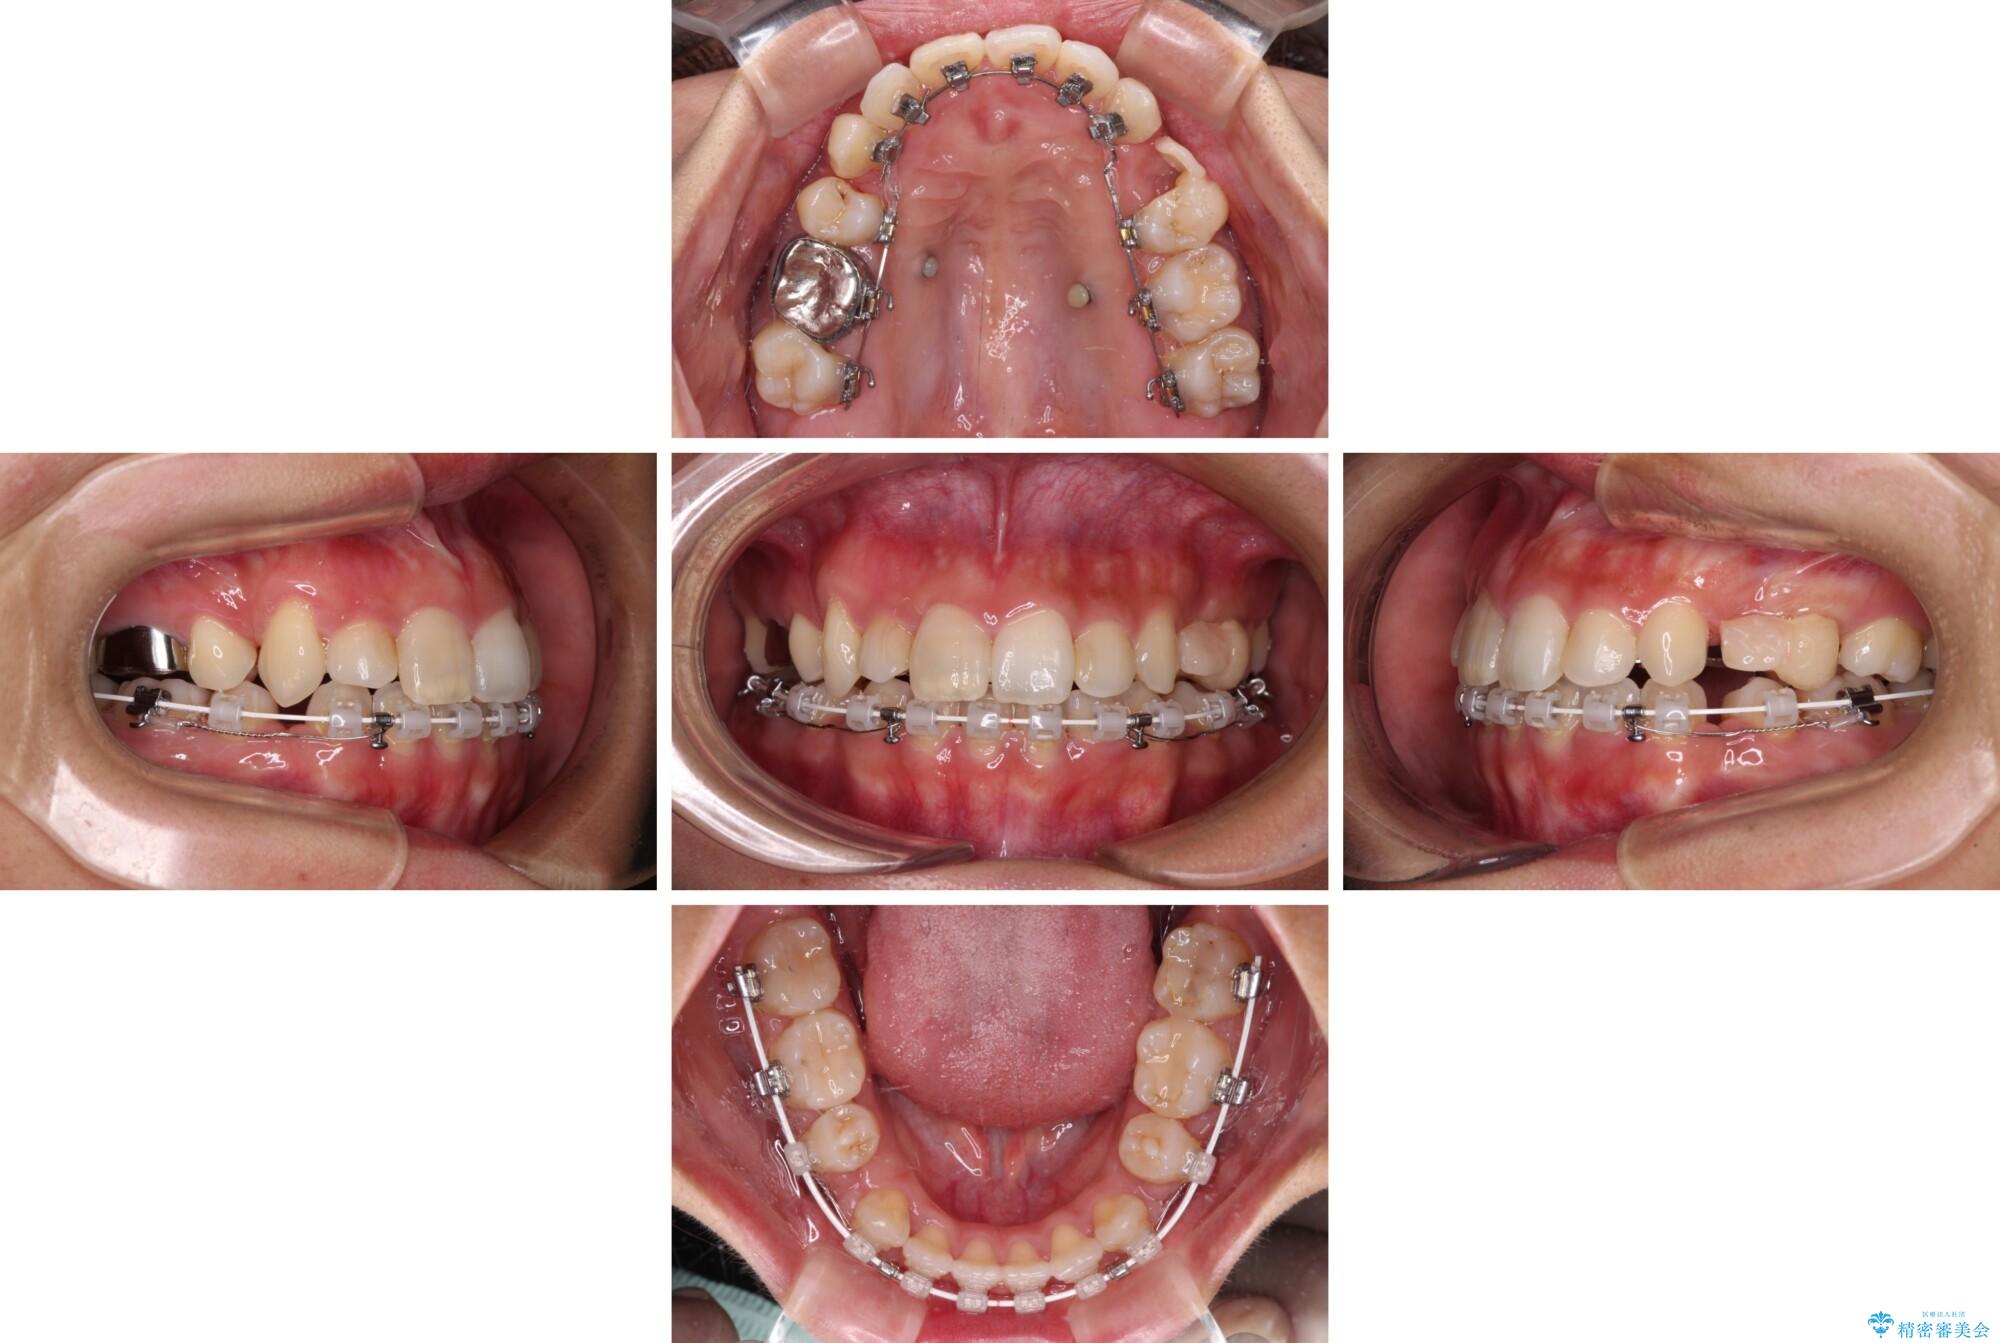

気になる八重歯 目立ちにくいハーフリンガルでの抜歯矯正の症例写真気になる八重歯 目立ちにくいハーフリンガルでの抜歯矯正